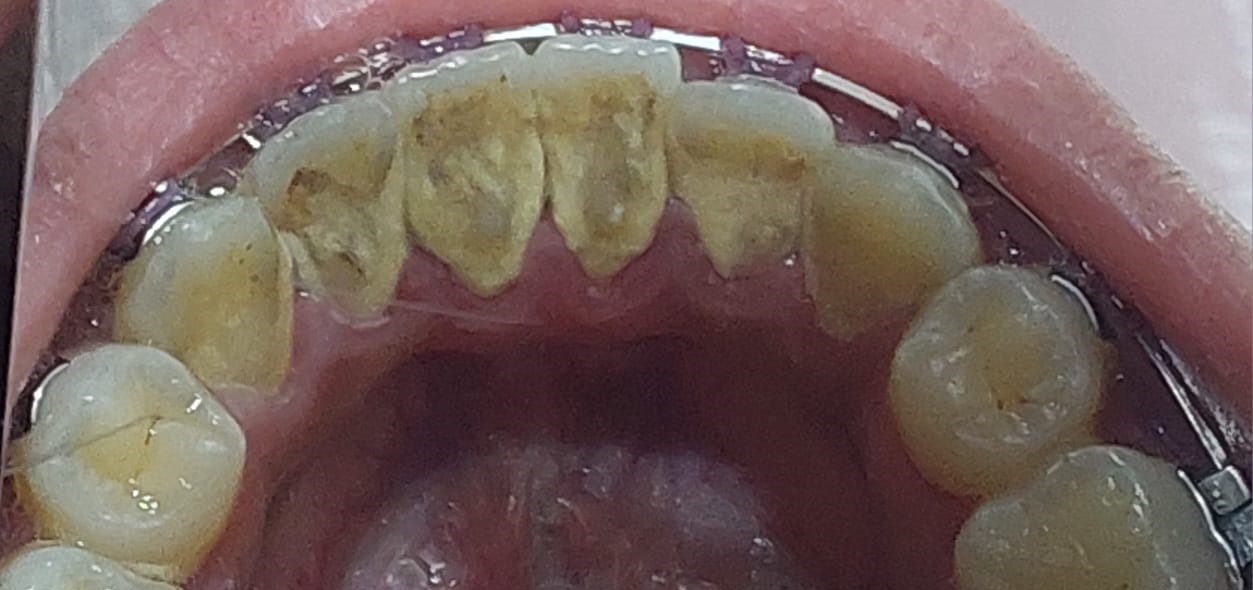

تجميل الأسنان الأمامية

تبييض وتجميل بالحشوات التجميلية

تنظيف الجير المتراكم

استعادة الابتسامة الكاملة و الحفاظ على صحة الاسنان